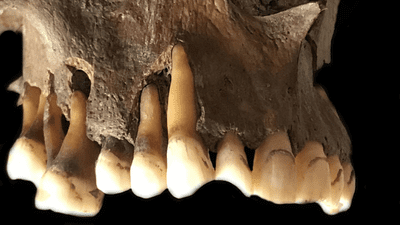

Fortunately, they found their ancient cold sore specimens in four individuals whose lives spanned a period of over 1,000 years. From these, they were able to extract viral DNA from the roots of teeth containing herpes genomes, with the oldest dating back to the late Iron Age around 1,500 years ago.